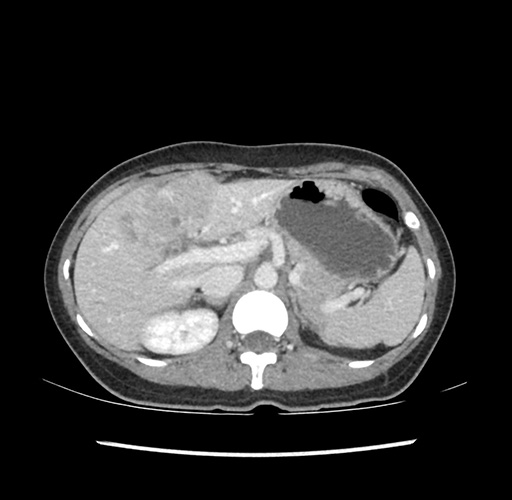

Imaging Analysis

Look through the patient's CT scan to identify any areas of concern for the necessary procedure.

Based on your CT findings, which issue(s) would give reason for "planned slowing down moment(s)" in this case?

Considering a standard left lateral sectionectomy procedure, what step(s) of the operation would you do differently in this case ?